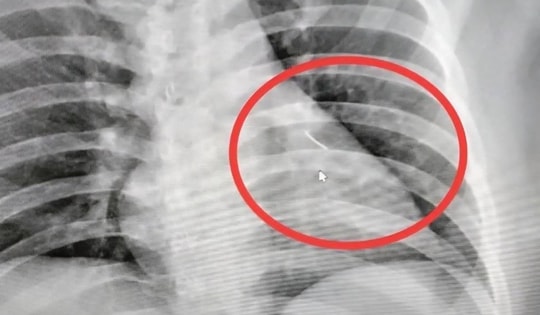

Người phụ nữ 54 tuổi đau ngực dữ dội, bác sĩ sốc nặng khi gắp ra thứ "đáng sợ" bên trong

30/09/2025 04:00

Người phụ nữ 54 tuổi đã vô tình nuốt phải một chiếc xương cá dài 4cm. Sau đó, bà bị đau ngực dữ dội và được đưa đến bệnh viện.